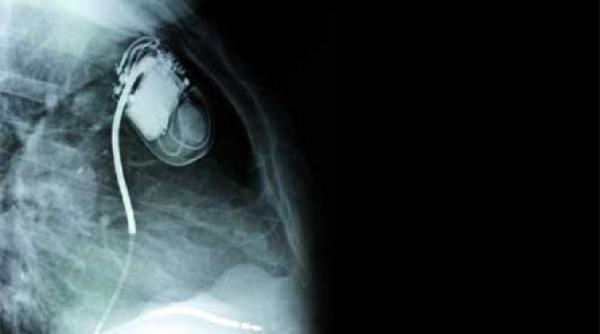

Pacemakerul – microtehnologia care bate cordul